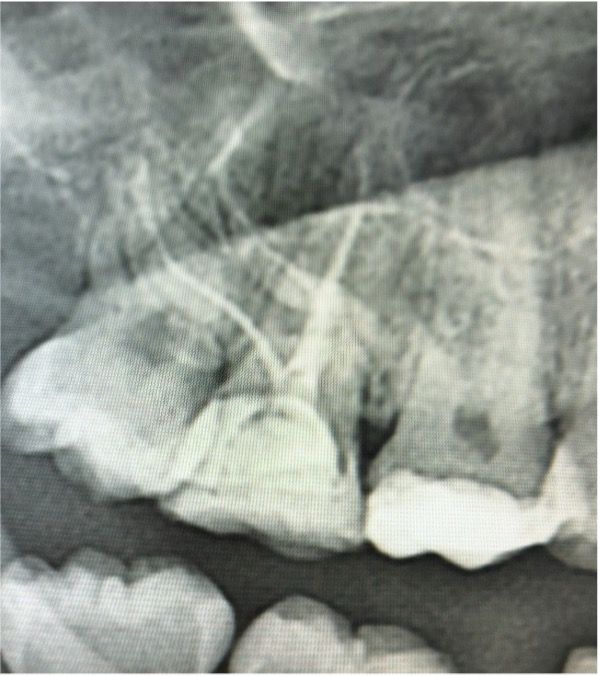

Kanal Dolumu: Şekillendirme ve final irigasyonunu takiben kanallar kurutulmuş ve tek seansta sızdırmaz bir şekilde üç boyutlu obturasyon işlemi gerçekleştirilmiştir. Alınan radyografilerde aşırı kurvatürlü kanalların orijinal anatomisine sadık kalındığı görülmektedir.

17 numaralı diş gibi ulaşılması zor ve anatomik olarak yüksek kurvatür riskleri barındıran bir dişte, kök kanal anatomisine saygılı bir preparasyon tekniği ve etkin bir irigasyon protokolü (EDDY) ile tek seans kök kanal tedavisi başarıyla uygulanmıştır. Aşırı madde kaybı olan diş, endokron restorasyonu ile hem biyomekanik hem de fonksiyonel olarak dental arka yeniden kazandırılmıştır.